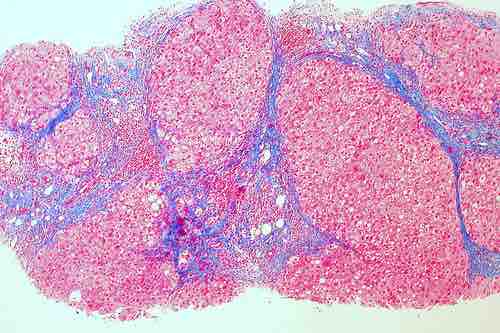

This image is a trichrome stain showing cirrhosis of the liver. Cirrhosis can be combatted by the portacaval shunt procedure, for which there have been numerous experimental trials using randomized assignment.

"Cirrhosis of the liver (trichrome stain) | Flickr - Photo Sharing!."